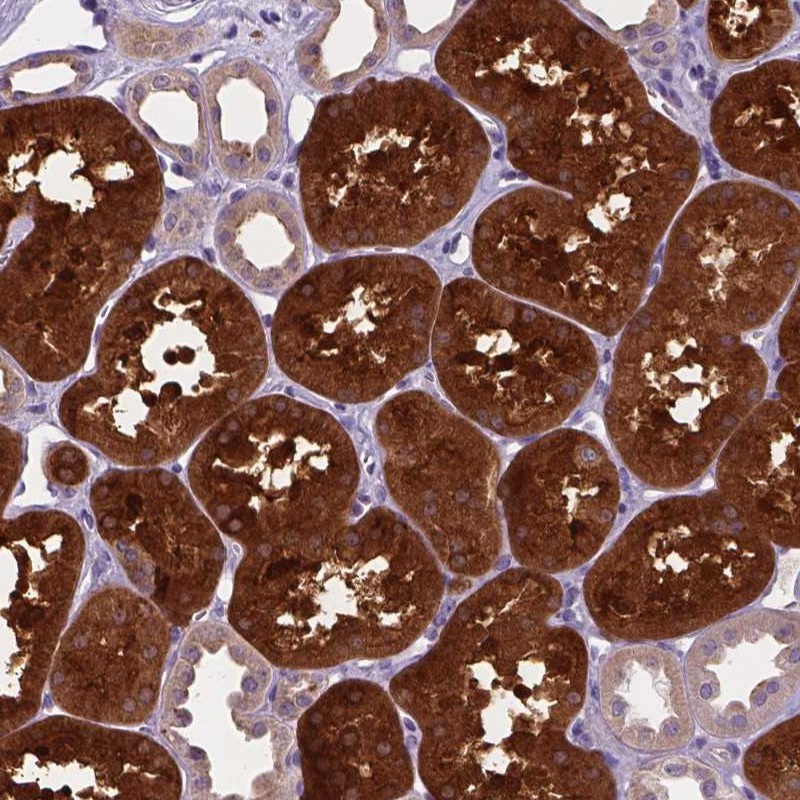

Immunohistochemical staining of human kidney shows strong cytoplasmic positivity in cells of proximal tubules.